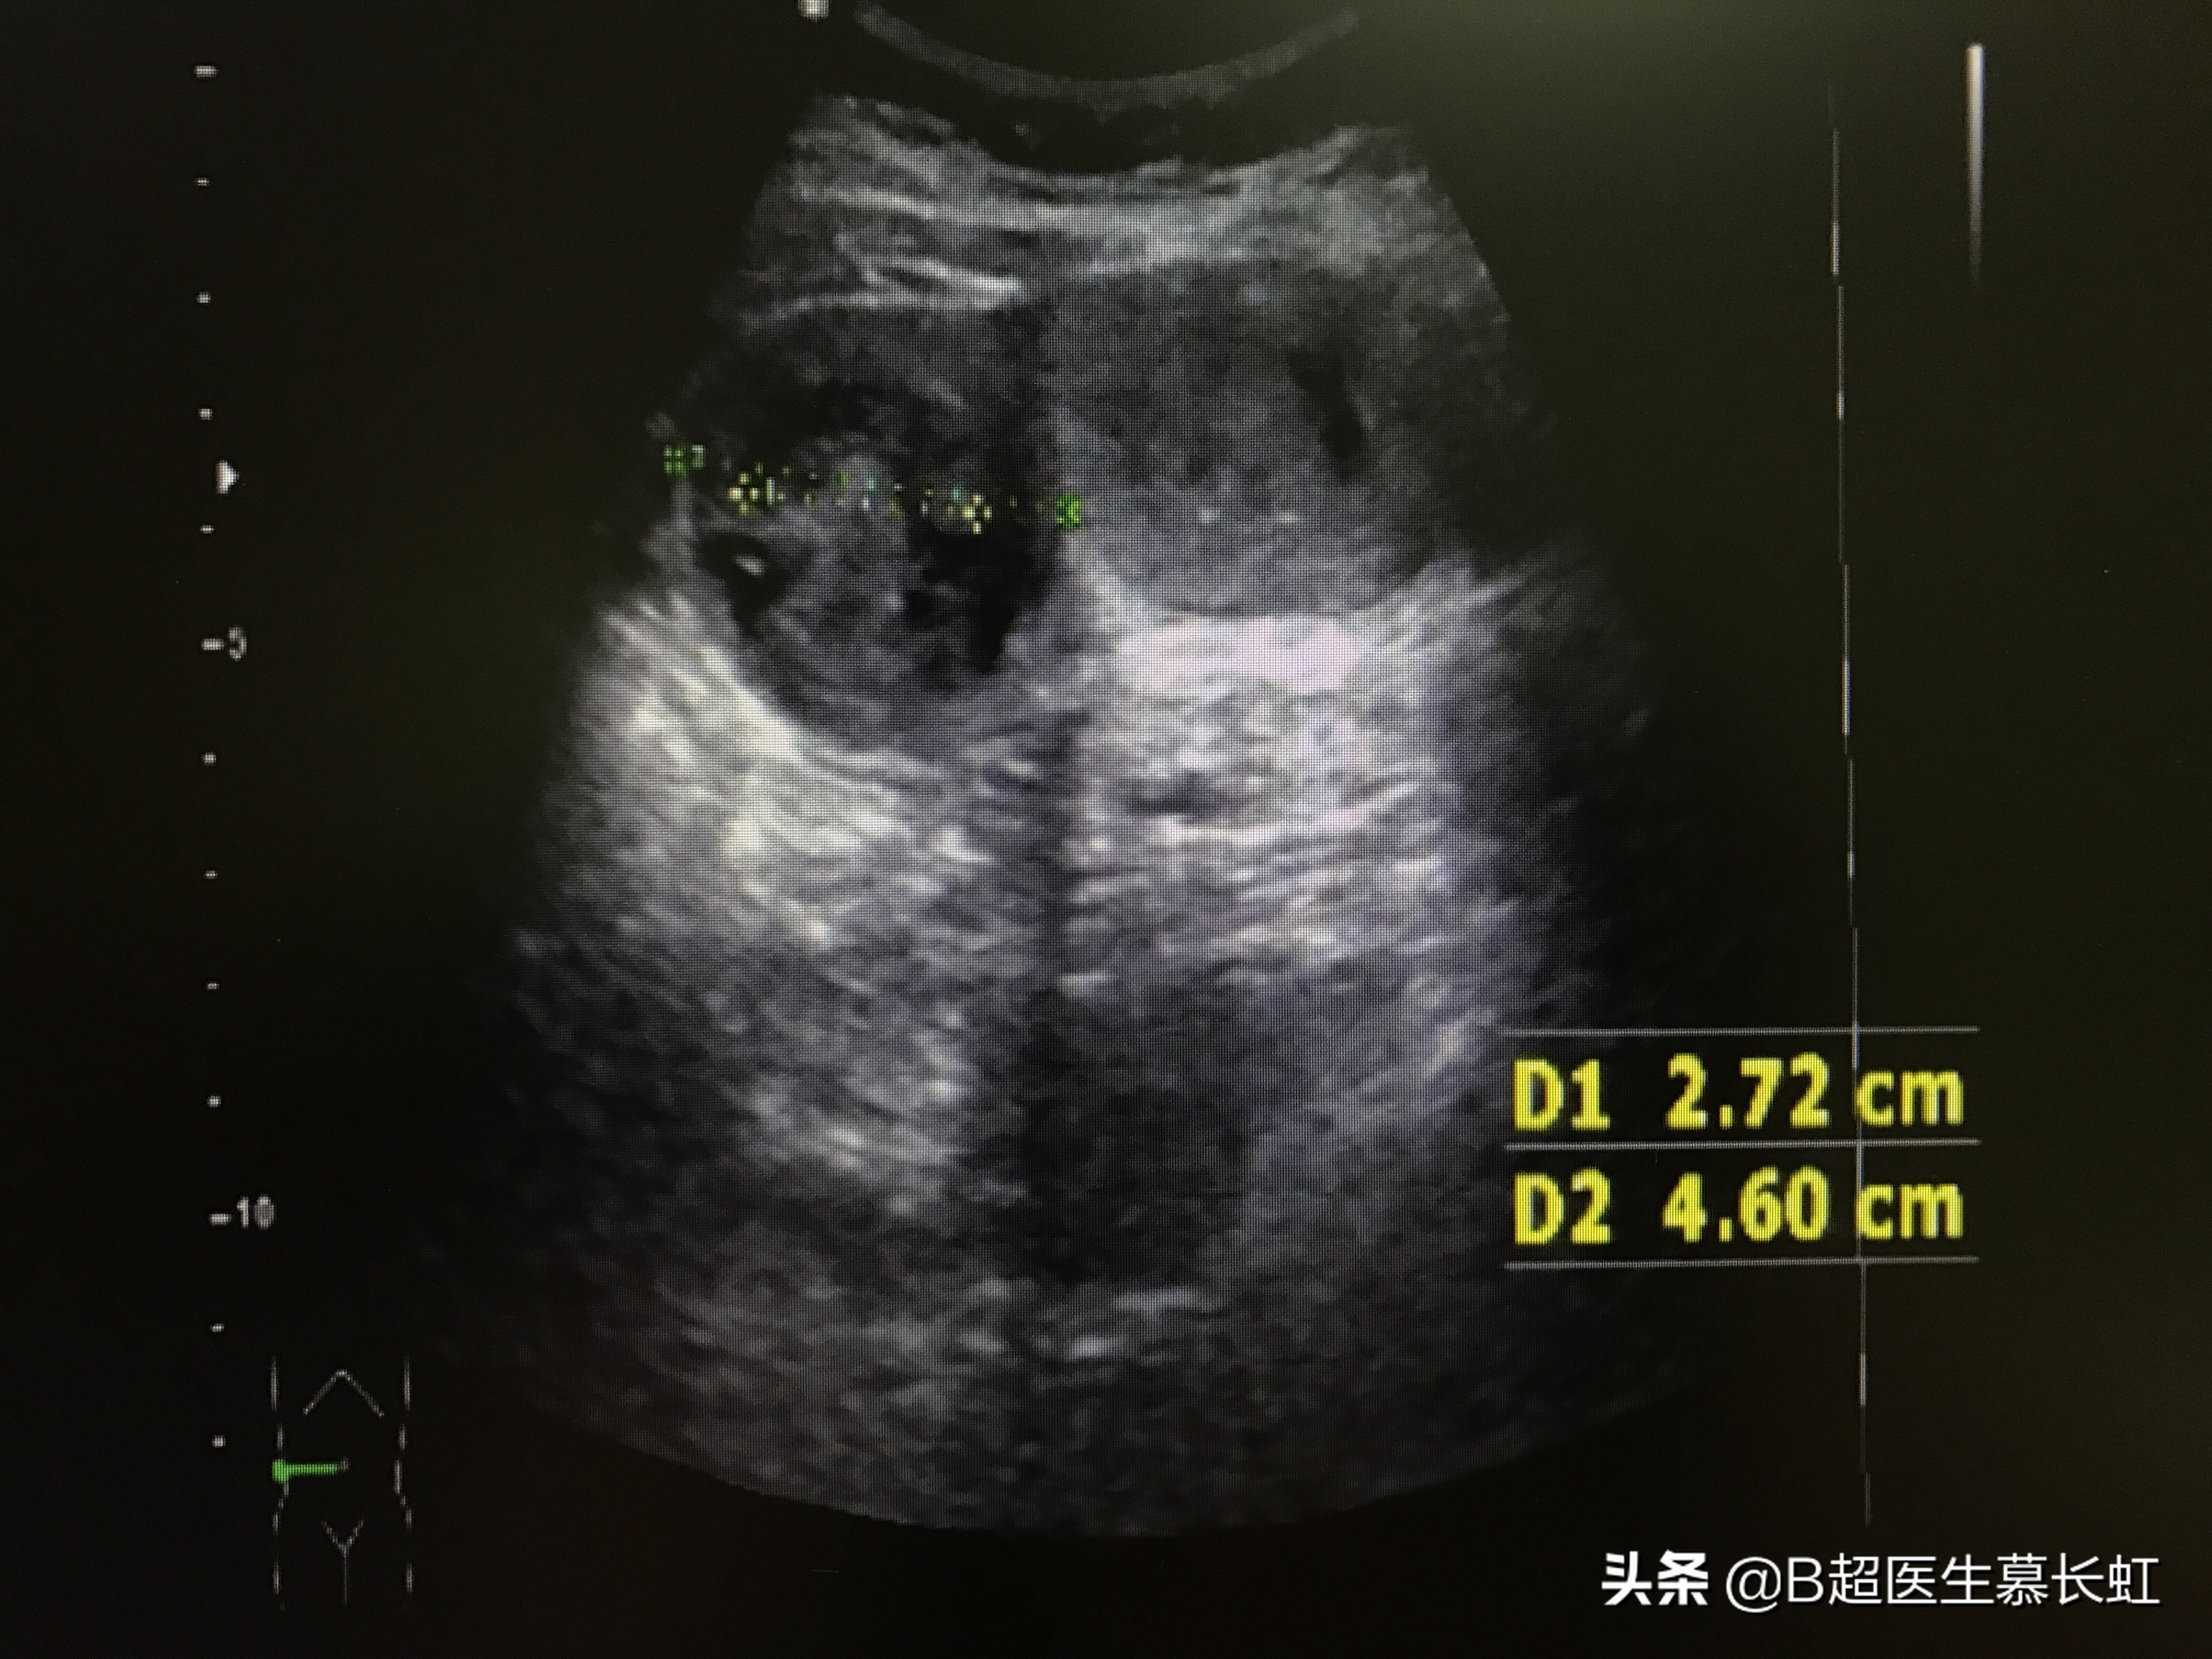

顺着扩张的肠管扫描下去,在阿姨的左上腹,发现肠管内有一个长条状的亮亮的实性团块,而在它之后的肠管,就是正常的了,所以可见罪魁祸首就是这个长条团块。

左上腹部肠管内,长条状实性团块

我的超声检查结果就是怀疑是这个团块导致了肠梗阻。

而又因为阿姨的胃做过部分切除,所以没有胃的幽门的阻挡,胃结石比较容易掉到肠管里去。现在那个胃结石(就是那个长条状的团块)已经走到了结肠脾曲的位置,也就是患者的左上腹部。